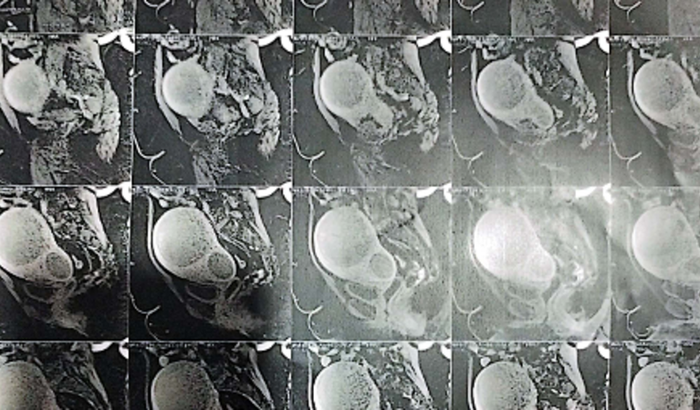

Vou contar um pouco da minha história, fui em uma felicidade radiante a uma tristeza em meses. Em novembro de 2022 descobri que estava grávida, que alegria, mesmo sem ser planejado eu e meu esposo e toda a família estávamos radiante, mais isso mudou em messes, já na primeira ultra descobri um mioma, como estava fazendo tratamento pelo SUS, me encaminharam para o tratamento de alto risco, passando os meses o mioma crescia cada vez mais, de 5cm na descoberta, na última ultra ele já estava em 13cm. Quando completei 6 meses de gestação, entrei em trabalho de parto prematuro, tentaram segurar com medicação, mais dia 15 de Março de 2023 meu filho Davi, veio ao mundo, em um parto super complicado e cheio de medos, ele lutou 1h58m pela vida dele😞 horas depois me informaram que meu filho não resistiu, foi a pior notícia da minha vida, fiquei sem chão e sem norte. Logo após tudo isso me internaram novamente, pois meu sangramento no pós parto não cessava, fiquei mais 5 dias internada, e fiz vários exames um turbilhão de emoções e sentimentos, mais no meu penúltimo dia internada, o médico entra no quarto, e me informa que pelas ultras meu mioma estava muito grande e meu útero também está com o vol. 1.200 e que teria que retirar meu útero😞, isso logo apos de perder meu filho, estava fraca sem forças e muito abalada , graças a Deus, minha família e a médica que fez o meu parto, não deixou isso acontecer, pois entraram com uma medição para tentar diminuir o volume do útero, com esse tempo um anjo apareceu em minha vida, o Dr. Michel Zelaquett do centro de mioma, consegui pagar a consulta com ele, pois ele só atende particular, me tirou todas as dúvidas e me disse que e possível sim preservar meu útero🙏🏻